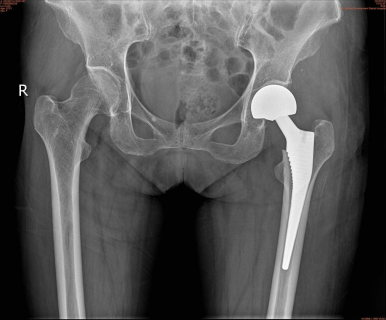

經醫師檢查,給予拍片后診斷為左側股骨頸骨折,需住院治療,在患者完善所有檢查后,骨科醫生經過與家屬溝通,詳細講解患者病情及治療方案后,決定為老人行人工髖關節置換術,經過充分術前準備后,在骨科、麻醉科、手術室等多科共同協助下,由骨科胡斌主任親自主刀,為劉婆婆實施人工髖關節置換術,因術前制定了完整的圍術期管理方案,成功縮短了手術時間,減少了術中出血,手術過程十分順利,術后三天劉婆婆能起床活動站立行走,一周后順利康復出院。